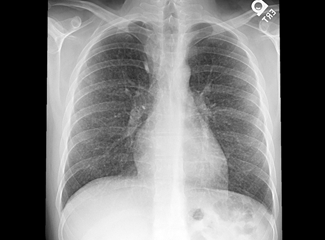

The following day the patient’s temperature was still elevated, ranging from 100oF to 102oF (37.7oC to 38.8oC) and his WBC count was still markedly elevated (between 21,000 and 22,000/µL). His breathing had become more rapid and labored. A CT scan of the chest with contrast (Figure 2) found mediastinal and hilar lymphadenopathy and a diffuse pattern of miliary nodules throughout both lungs. The findings were highly suggestive of tuberculosis (TB).